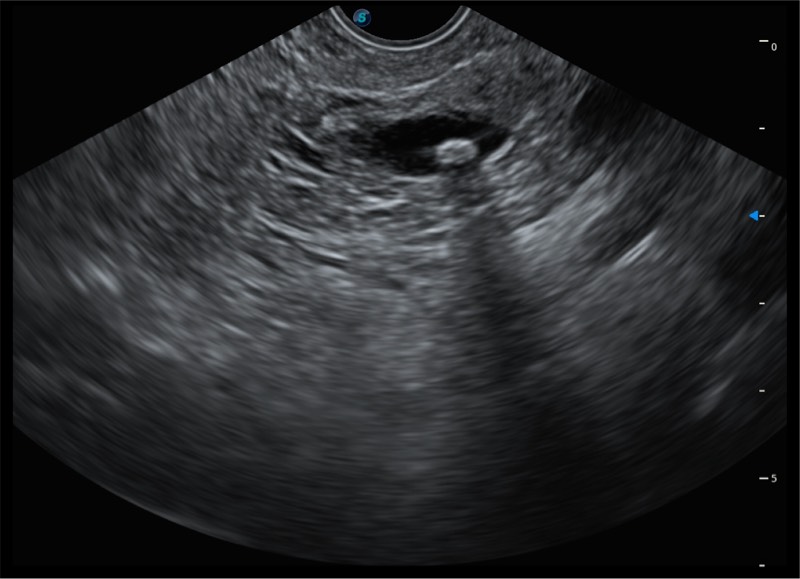

搭载百万级CMOS成像技术

及自主研发凸阵换能器,

可呈现优质的内镜和超声画面

基于二十年的超声技术积累,银河集团官网提供了最新一代的独立超声主机,在提供高质量图像的同时满足多学科使用。具备常见多普勒技术并提供弹性成像、声学造影等高端影像技术。新一代传感器具有更强的抗干扰能力并减少图像伪影。

150°超声扫描角度

4-12MHZ宽频输出